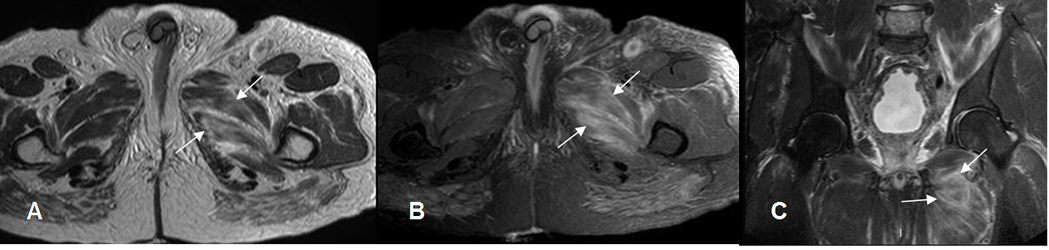

Fig 21. Distensión muscular grado 2.

A: RM axial en T1. Alteración en la señal de los músculos aductor mediano y mayor por edema y sangrado subagudo.

B: RM axial y C: RM coronal en STIR. Músculos hiperintensos y con ruptura de algunas fibras, por distensión grado 2.